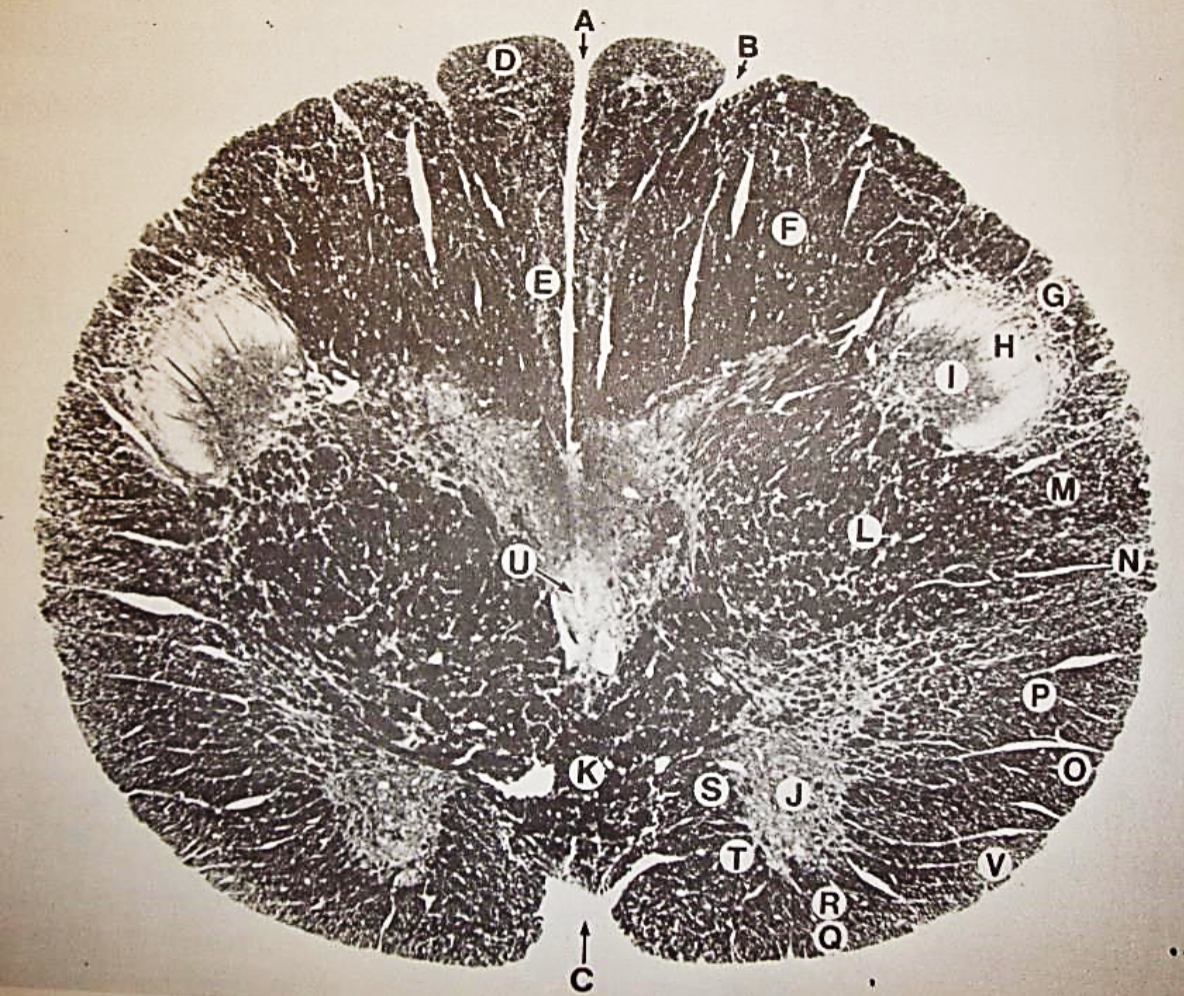

A

posterior median sulcus

B

posterior intermediate sulcus

C

anterior median fissure

D

gracile fasciculus

E

Gracile nucleus

F

fasciculus cuneatus

G

spinal trigeminal tract

H+I collectively

spinal trigeminal nucleus

J

Accessory nucleus

K

pyramidal decussation

L

lateral corticospinal tract

M

rubrospinal tract

N

posterior spinocerebellar tract

O

anterior spinocerebellar tract

P

lateral spinothalamic tract

Q

anterior spinothalamic tract

R

lateral vestibulospinal tract

S

medial longitudinal fasciculus

T

tectospinal tract

U

central canal